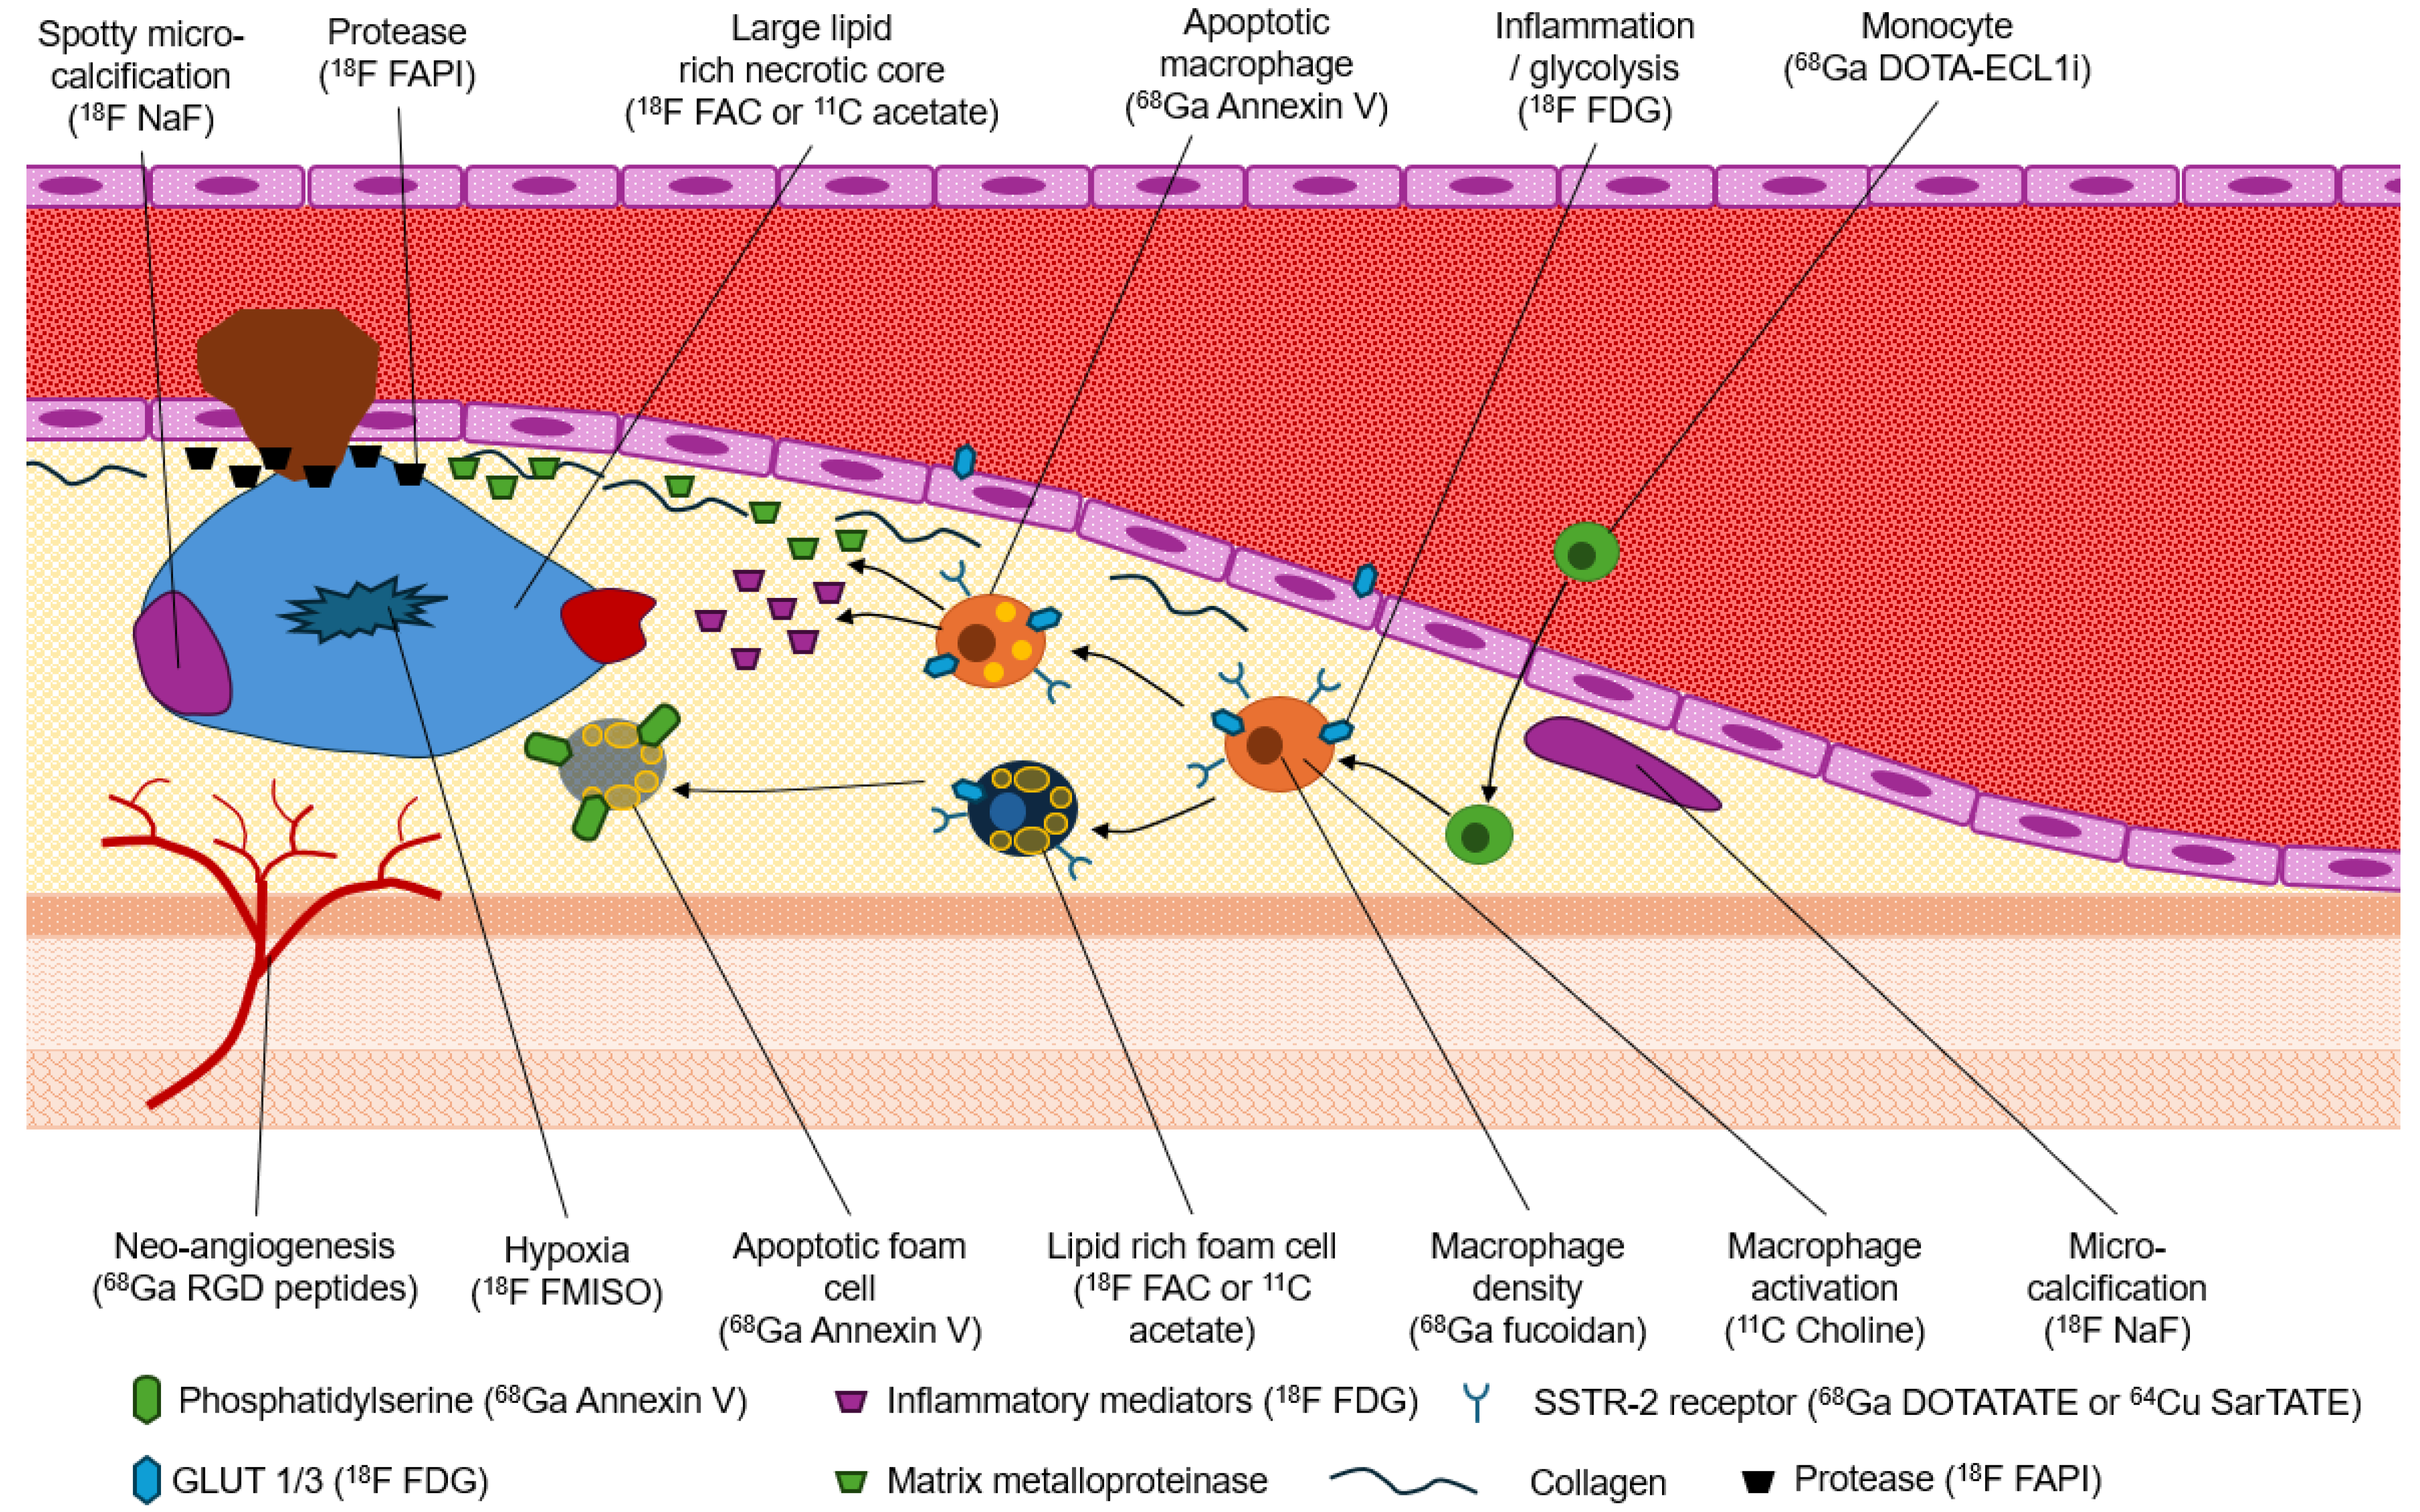

1.3. Molecular Imaging of the Hallmarks of Plaque Vulnerability

1.4. Inflammation

1.5. Micro-Calcifications